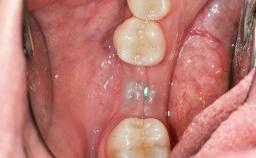

Soft-Tissue Volume Augmentation Using a Connective-Tissue Graft Harvested from the Maxillary Tuberosity

Soft Tissue Grafting Simultaneous